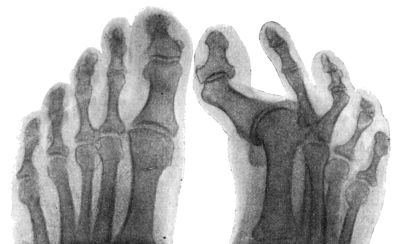

| 157. | Radiogram of Hallux Valgus | 296 |

| 158. | Radiogram of Hallux Varus or Pigeon-Toe | 298 |